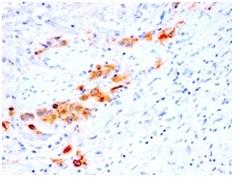

Positive Control

Cervix or Tongue Squamous Cell Carcinoma